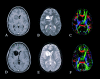

Fig 2.

Patient 2. Preoperative (A–C) and postoperative (D–F) axial images of a left frontal pilocytic astrocytoma: contrast-enhanced T1-weighted images (A and D), T2-weighted images (B and E), and directional color maps (C and F). Before surgery, DTI reveals decreased FA (diminished blue in C) and posteromedial displacement of the left PLIC (arrow in C). After surgery, DTI shows both restored FA (normal blue in F) and normal positioning of the left PLIC.